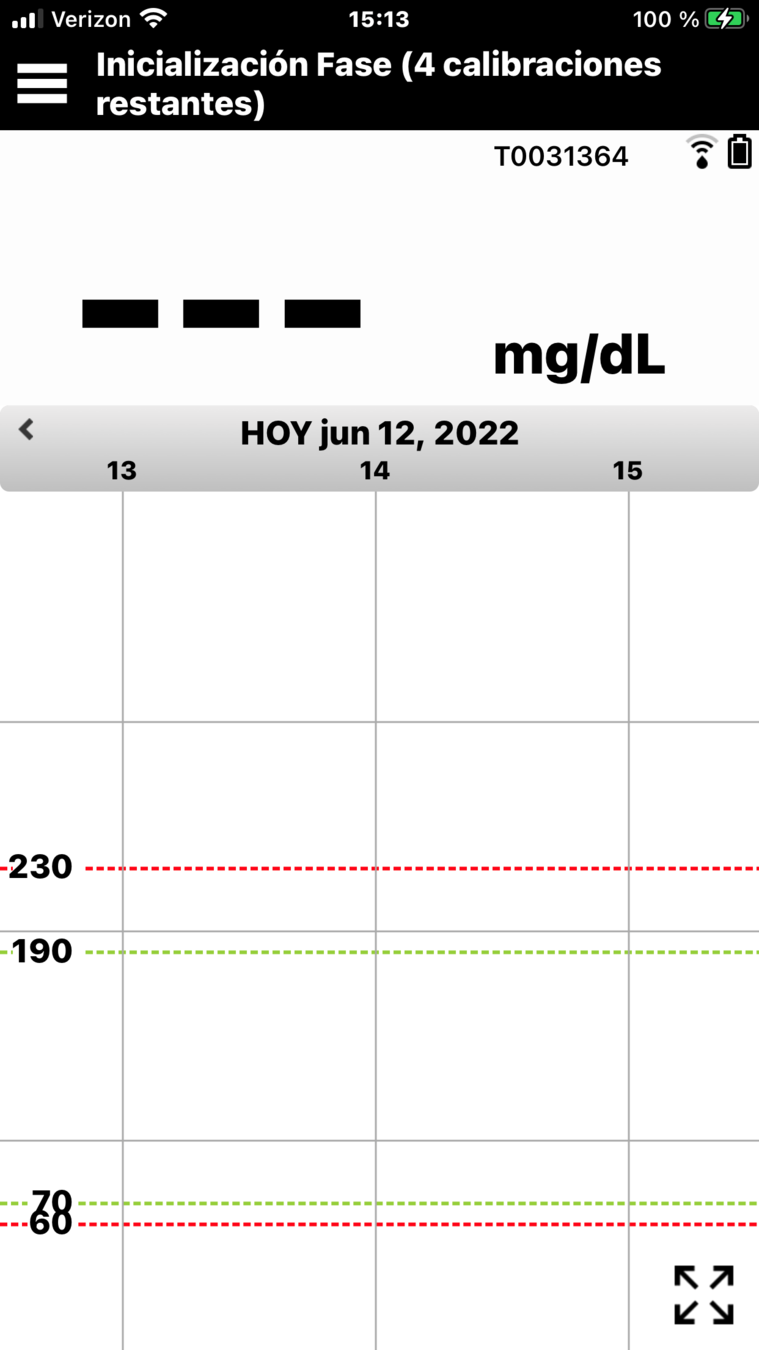

Y, en la parte inferior, se encuentra el gráfico de tendencia de la glucosa.

Las líneas discontinuas rojas indican los niveles de alerta de glucosa alta y baja, y las líneas discontinuas verdes indican el intervalo objetivo.

Todos los eventos que introduzca en la aplicación (como una calibración, comida, ejercicio

o insulina) o las alertas que reciba, se mostrarán en el gráfico de tendencia con un icono.